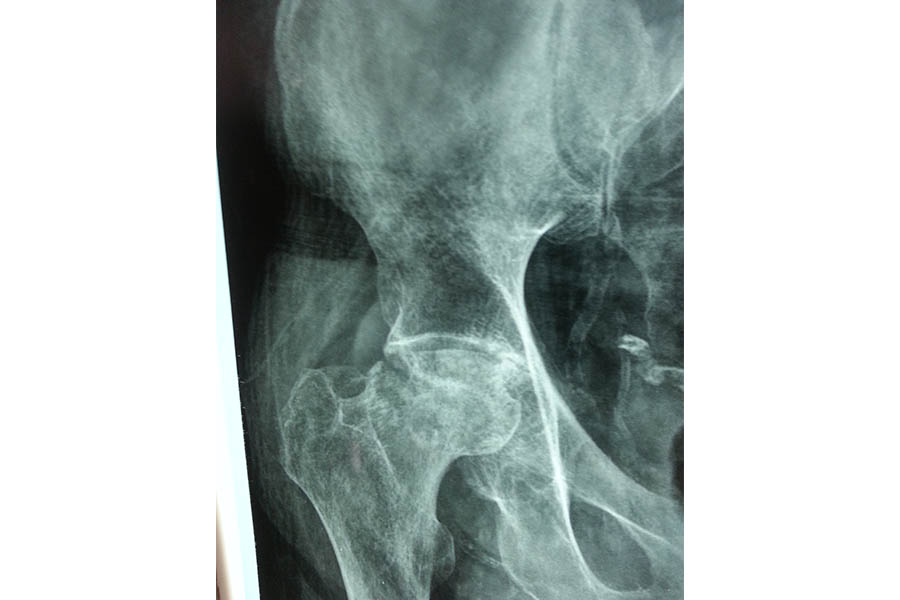

Total Hip Replacement

Difficult Replacement

Case 1